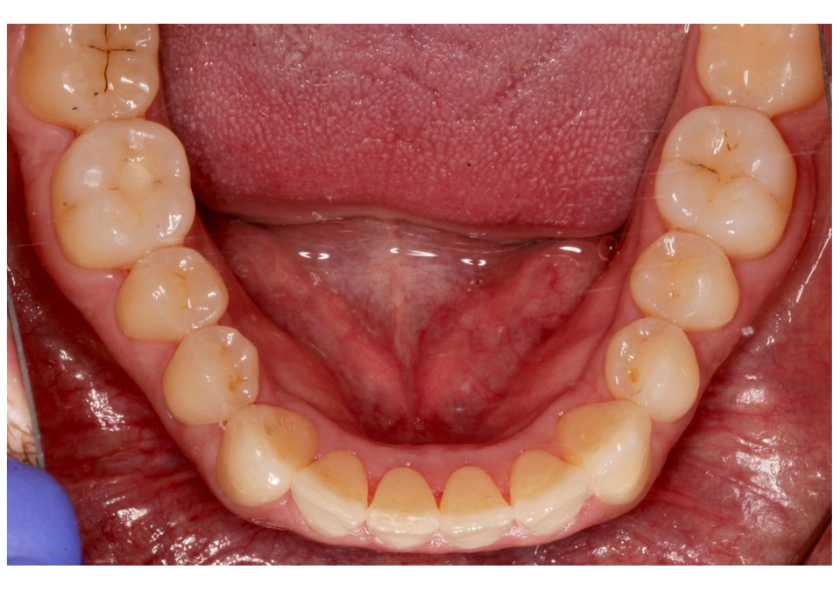

Este paciente acudió a Clínica Dental Urumea para mejorar la estética de su sonrisa. Primero se realizó un tratamiento de ortodoncia con alineadores transparentes Invisalign, para alinear y corregir la mordida cruzada.

Posteriormente, se realizaron blanqueamientos ambulatorios para mejorar

En este caso se ha optado por alineadores Vivera como método de retención.